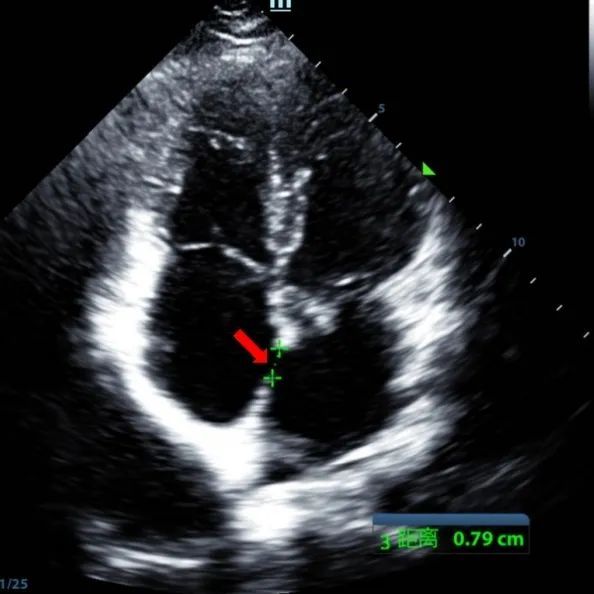

Ein 9-jähriger Mann mit secundum ASD (7,5-7,9mm) wurde mit einem MemoSorb-BDASD-I 12-mm-Okk luder und einem 12F-Fördersystem behandelt. Vor dem Eingriff wurden keine Komplikationen oder Komorbiditäten festgestellt.

Serial echocardiographic follow-ups showed stable device position and favorable cardiac remodeling. Gradual degradation confirmed the occluder's long-term safety and efficacy.